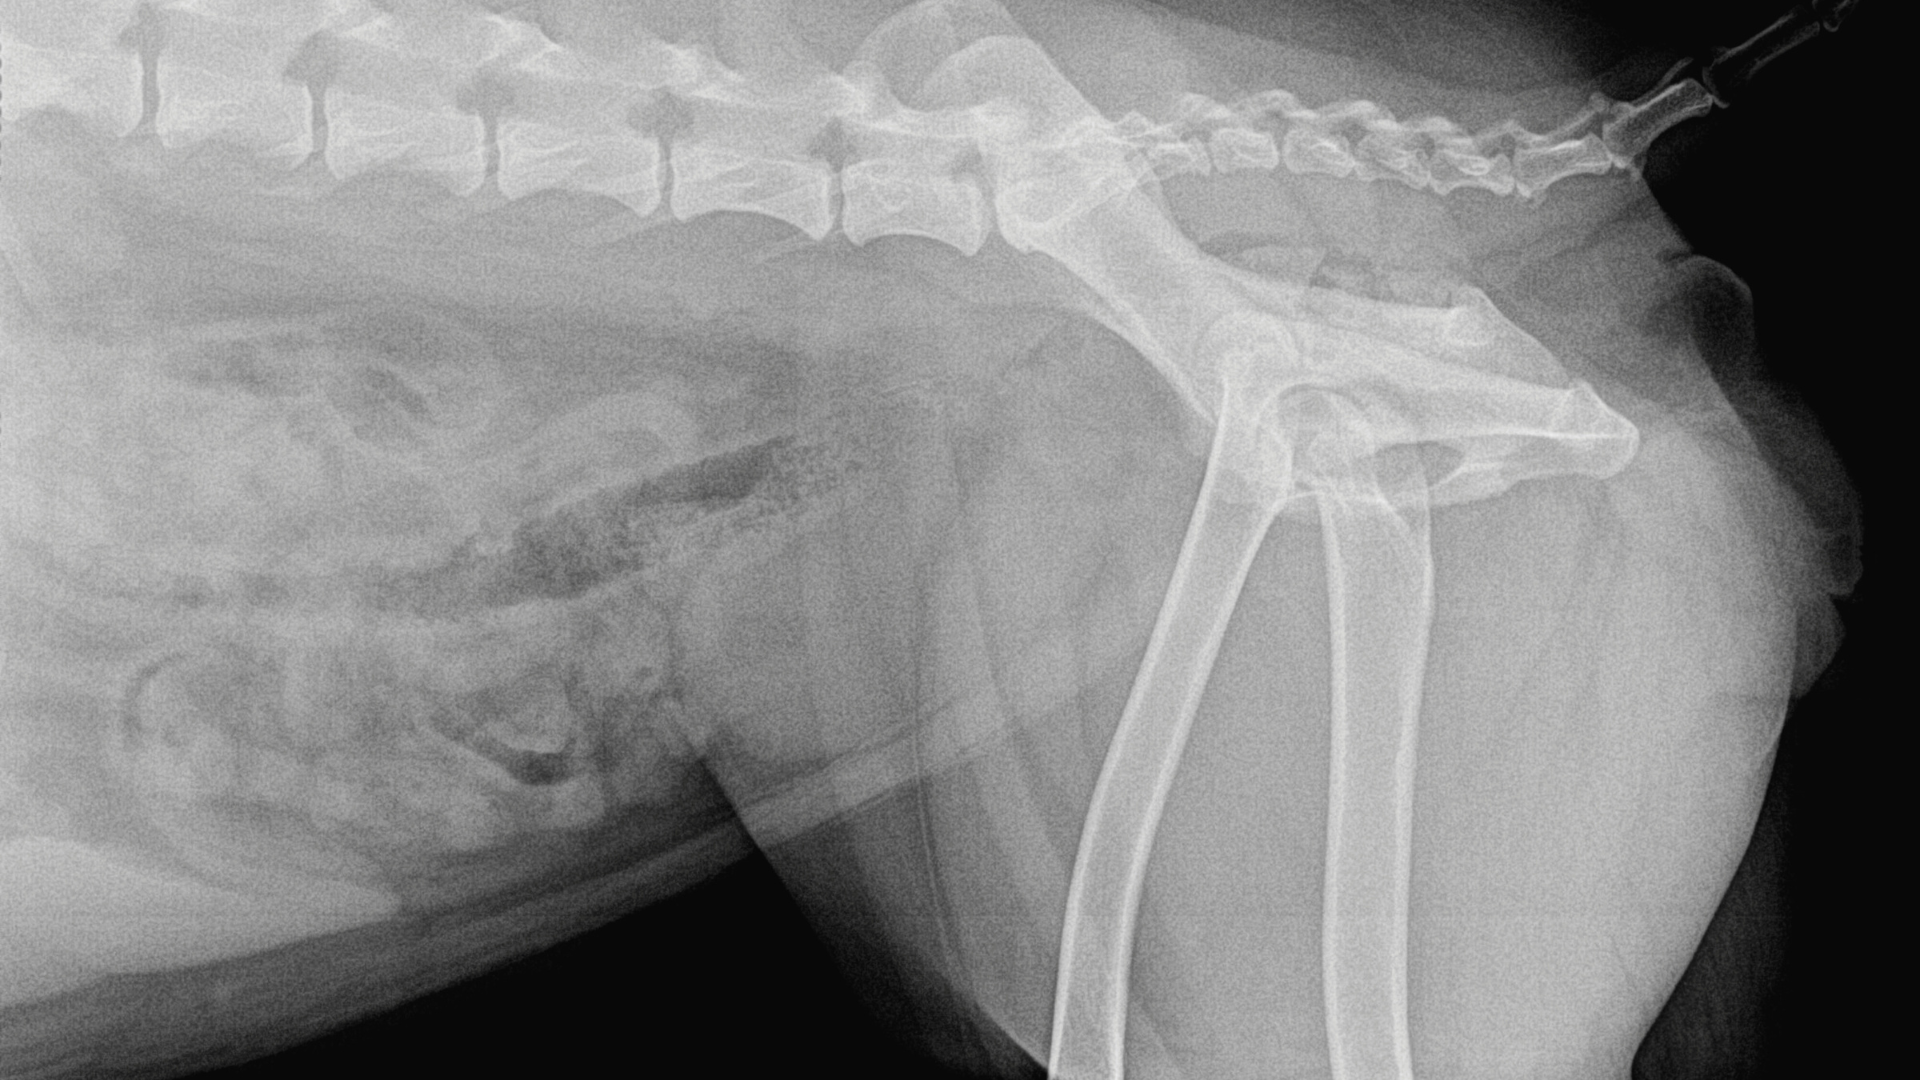

2. Canine Hip Dysplasia

Canine hip dysplasia is a painful condition in which the hip joint forms improperly, leading to looseness, pain, and arthritis. It often affects large breeds and can cause stiffness, difficulty moving, and reduced mobility. The signs and symptoms of canine hip dysplasia are as follows: